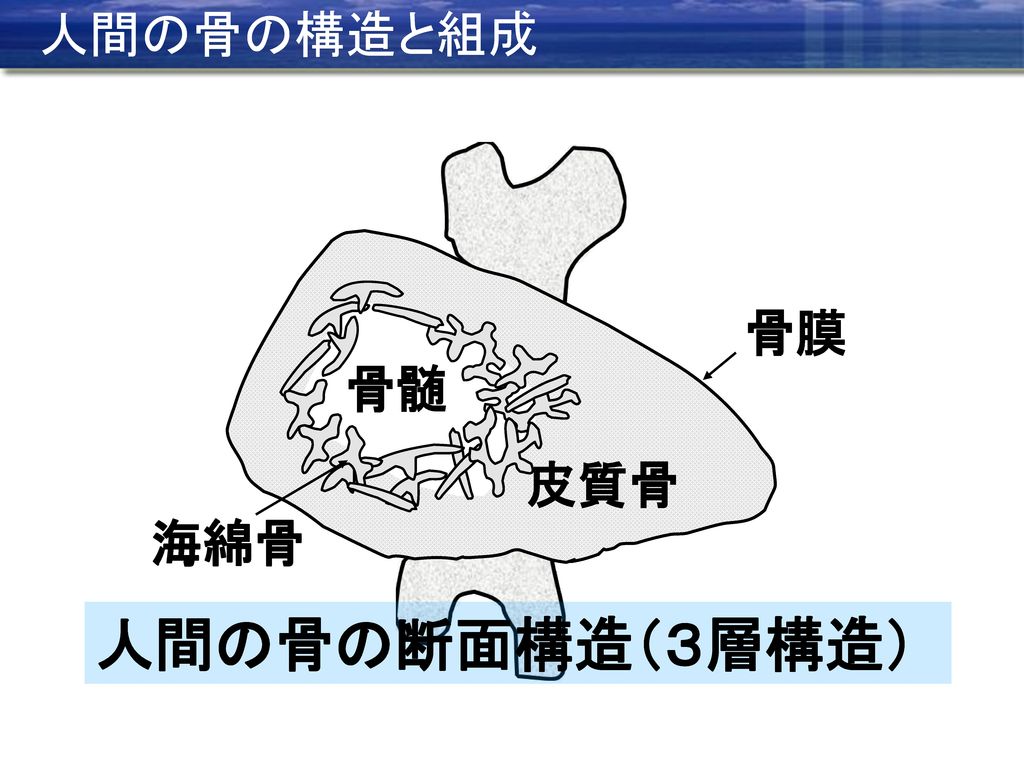

人間 骨 構造

人間 骨 構造. 人間の ほね 骨は、全部で何本あるの 生まれたばかりの赤ちゃんの骨の数は、約305個もあります。それが、成長し ていくにしたがって、はなれていた骨がくっついて一つになったり、いくつかの骨. 次は、関節の構造の解説です。 関節の構造 人間のカラダには約650の筋があり、 カラダを動かすことに使われる筋(骨格筋)は、 そのうちの約400です。 一部の例外を除いたすべての骨格筋は、 別々の骨と骨に「関節」を介してつながっています。 ですので、. 腱が骨や関節の近くを通過するところに存在し,腱の方向 を変える働きをする。 骨の組織構造7 緻密質にみられる骨の典型的な組織構造を,ハヴァース 系という。血管の通路であるハヴァース管Haversian canal を,厚さ数μmの骨層板bone lamellaが同心円状に取り巻.

骨構造 人体のあらゆる骨は、骨のあるプレート、クロスバー、そして梁で構成されています。 唯一の違いは、これらの要素のコンパクトさです。 管状の骨の部分では、外側の骨の物質は密で、内側の方がより砕けやすいです。 人間の下肢の骨格構造は. 階層構造 人体を要素に分解しながら見てゆくことも可能である。 骨は細かく分類すると0 人間は、意識的であれ無意識的であれ、人体をコミュニケーションの媒体としても用いている。. よくクイズで問題になることがありますが、人間の骨はいくつあるかご存知ですか? 答えは 成人は約6個 といわれています。 「約」と書いたのは、人によって欠けている骨もあるからです。.